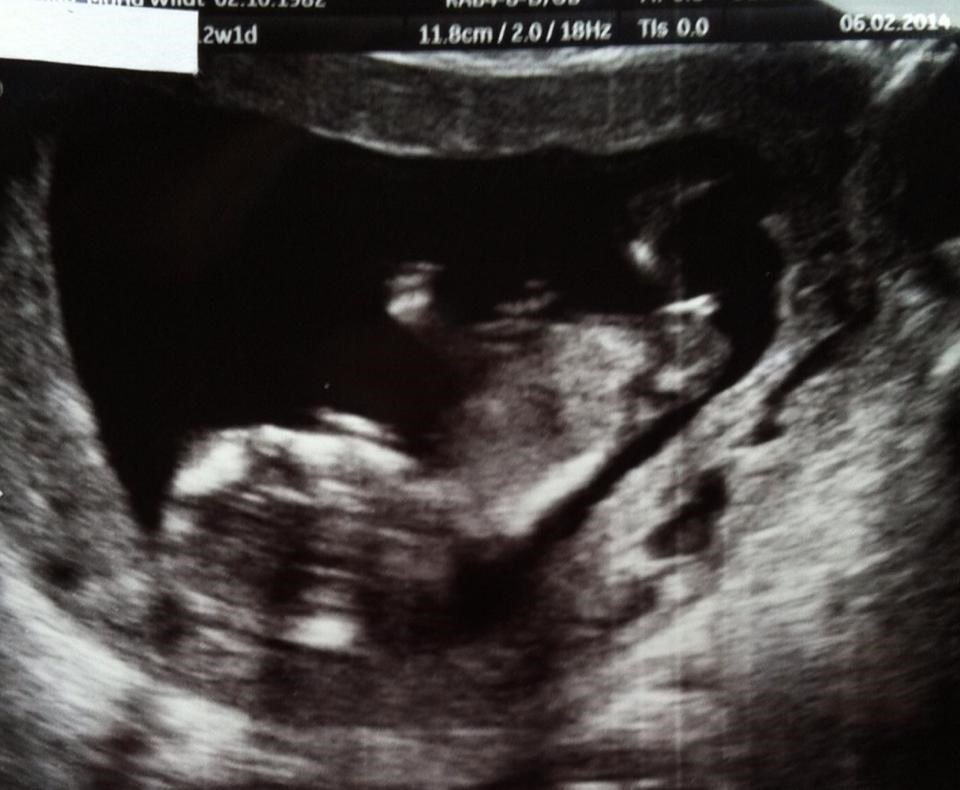

Alexander&Lærke skriver:

Tillykke med både graviditet og nakkefold scanningen.... Hvornår forventes bebs at ankomme?

Termin er sat til 15 August